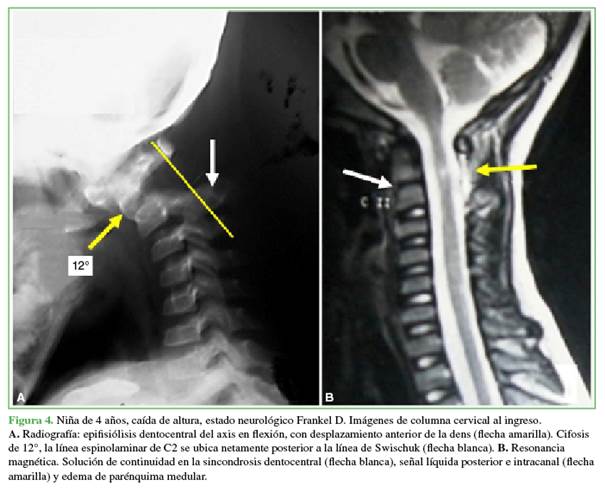

Ciertas afecciones traumáticas o congénitas ajenas al sector C2-C3, como fracturas o epifisiólisis del axis e inestabilidad sagital C1-C2, pueden alterar sensiblemente la LDS (Figuras 3 y 4). Algunas observaciones ulteriores a la publicación del artículo de Swischuk y otras devenidas de nuestra práctica cotidiana motivaron esta investigación cuyo objetivo consistió en llevar a cabo una revisión bibliográfica sobre la interpretación y la limitación diagnóstica de la LDS con ilustración de casos clínicos.

Al Dr. Patricio Manzone por compartir el Caso de la Figura 4.